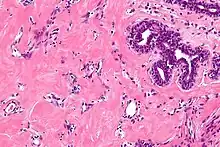

| High magnification micrograph of pseudoangiomatous stromal hyperplasia showing the characteristic small, anastomosing blood vessel-like channels. H&E stain. | |